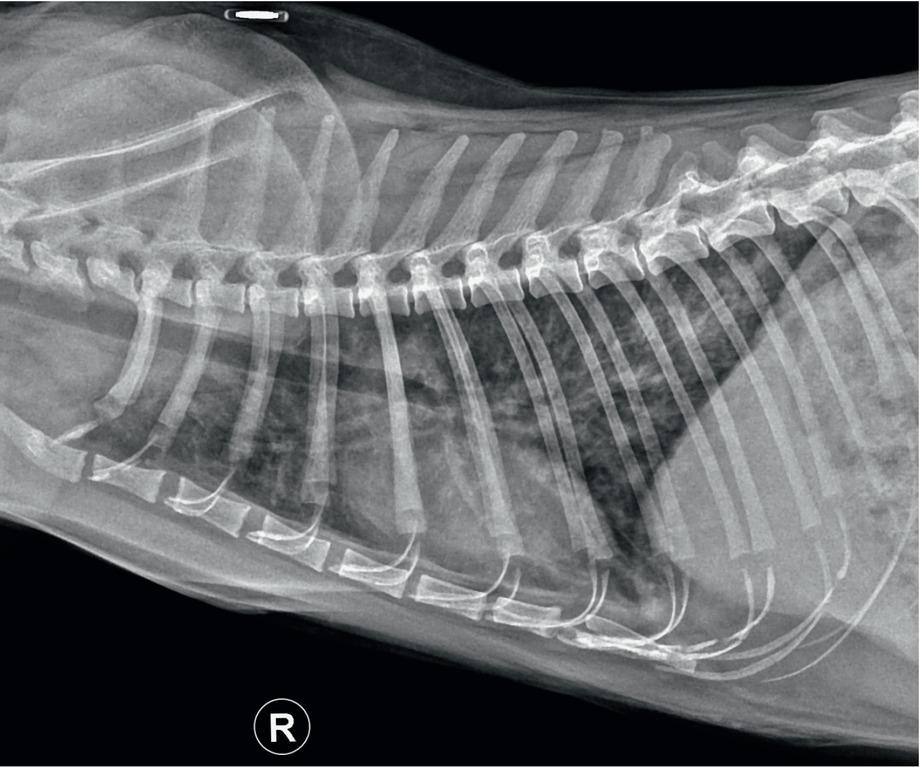

Fig. 1